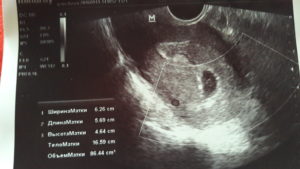

При помощи УЗИ гинеколог сможет увидеть не только угрозу, но и ее возможную причину (аномалия развития плода, предлежание и отслойку плаценты, признаки внутриутробного инфицирования, нарушение кровотока). При ультразвуковом исследовании всегда можно оценить состояние малыша и если потребуется, принять все возможные меры по сохранению беременности и спасению жизни плода.

Доктор произведет осмотр, во время которого оценит состояние матки и шейки матки, а также назначит УЗИ для оценки состояния плода.

Именно поэтому после того как случился выкидыш обязательно необходимо выполнить контрольное ультразвуковое исследование органов малого таза, чтобы убедиться в отсутствии в матке тканей плода. Если они были обнаружены, то потребуется выполнение гинекологической чистки.